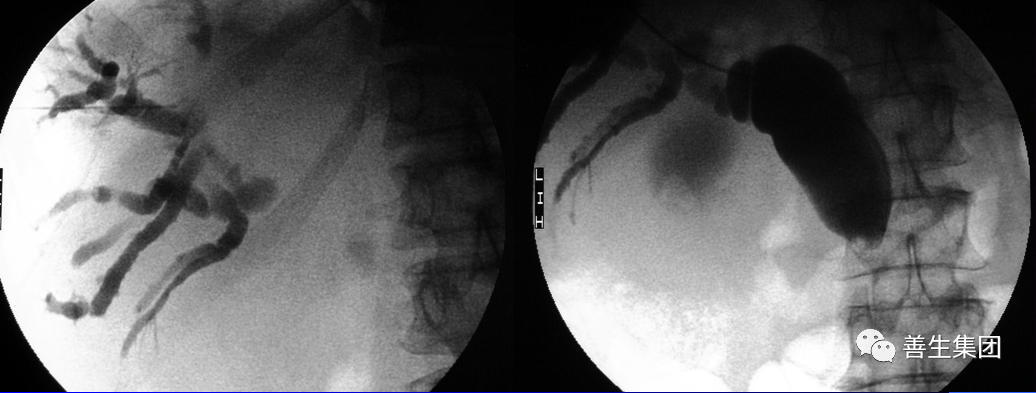

右肝MT,伴梗阻性黄疸。先穿刺右侧胆管,发觉左侧胆管更顺,改穿左侧。

胆管支架什么样子经皮肝胆管穿刺置管引流术(PTCD)及胆道内支架临床应用_https://www.jmylbn.com_新闻资讯_第23张

导管、导丝通过狭窄段

胆管支架什么样子经皮肝胆管穿刺置管引流术(PTCD)及胆道内支架临床应用_https://www.jmylbn.com_新闻资讯_第24张

金属内支架+局部狭窄扩张后

胆管支架什么样子经皮肝胆管穿刺置管引流术(PTCD)及胆道内支架临床应用_https://www.jmylbn.com_新闻资讯_第25张

金属内支架+引流管